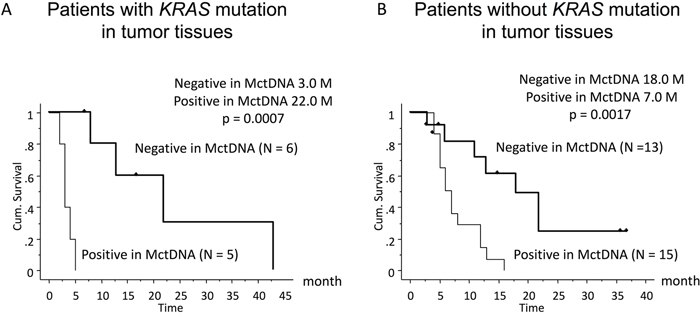

In 29 patients with the MT, MctDNA was detected in 23 patients (79.3%) (Figure 1A). Among 18 patients who underwent second-line or subsequent treatment lines, MctDNA was detected in 17 patients (94.4%). Details of the clinical course of these 29 patients is shown in Table 1. The median value of MctDNA was 64.0 copies/well (3.2–45800) for the number and 10.10% (0.26–93.60) for the ratio in these 29 patients (Figure 1B and 1C). Comparing progression-free survival (PFS) of the first-line treatment between patients with MctDNA and without, there was a significant difference in PFS (Figure 2A), with a worse outcome in patients with MctDNA (22.0 vs 3.0 months, p = 0.0007). Most patients showed a continuous change with increasing MctDNA (Figure 3A and 3C). Four patients had a stable MctDNA level, suggesting a long stable disease (Figures 3B and 4A), and two patients showed a quick decrease in MctDNA with shrinkage of tumors in response to treatment (Figure 3D and Figure 4G).

Figure 2: Comparison of progression-free survival (PFS) in patients treated with the first-line therapy according to KRAS status in blood. Patients with KRAS mutations in tumor tissues (left) and those without KRAS mutations (right).

In 56 patients with the WT, MctDNA was detected in 28 patients (50.0%) (Figure 1A). Details of the clinical course of these 56 patients is shown in Table 2. MctDNA was detected in patients treated with anti-EGFR antibody as well as those treated with other drugs such as anti-vascular endothelial growth factor (VEGF) antibody, regorafenib, and TAS-102. Cytotoxic agents without targeted therapies also showed the emergence of MctDNA (Table 3). The median value of MctDNA was 9.1 (2.6–414) for the number and 0.22% (0.002–14.2) for the ratio (Figure 1B and 1C). The median value of MctDNA for the number detected in patients with the WT was 1/7 of that in patients with the MT, suggesting that about 1/7 of tumor cells (14.7%) in patients with the WT might have the KRAS mutation. Comparing first-line treatment between patients with MctDNA and those without, there was a significant difference in PFS (Figure 2B), showing a worse outcome in patients with MctDNA (18.0 vs 7.0 months, p = 0.0017). Most patients showed intermittent changes in elevation; with low levels of MctDNA generally (Figure 3E and 3F), four patients showed a continuous change with an increase (Figure 3G), and five patients showed a transient change with a spike in elevation (quick elevation and disappearance) (Figure 3H), with close to 10 times the amount of MctDNA as the intermittent change in elevation (Figure 3F). Initial detection of MctDNA in WT patients treated with anti-EGFR antibody was likely prior to radiological disease progression (Figure 1D).

MctDNA was seen in the blood of patients with not only the MT but also the WT in tumor tissues. MctDNA was observed during treatments with various drugs such as anti-VEGF antibody, regorafenib, TAS-102, and anti-EGFR antibody. Regardless of the KRAS status in tumor tissues, patients with MctDNA in blood showed poor PFS with first-line treatment. KRAS monitoring identified dynamic changes in MctDNA, such as continuous, intermittent, and transient changes, which corresponded with drug response or resistance. It is possible that the disappearance of MctDNA could be involved in recovery of sensitivity to anti-EGFR antibody [19].